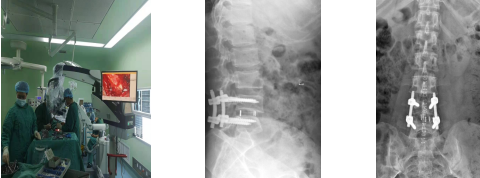

多年以来,神经外科习惯被称为“脑外科”。这主要是由于长期忽视神经脊柱亚专业的发展。神经脊柱亚专业是神经外科的重要组成部分,神经外科的微创理念和显微技术在脊柱脊髓的创伤、退变、肿瘤、畸形等各类疾病的外科治疗中具有独特优势。刘进平老师带领我院神经外科团队开展新技术“显微镜下后路微创腰椎融合术”治疗“腰椎管狭窄症”,“腰椎滑脱症”取得了良好的临床疗效,受到患者和家属的好评。同时,通过系列学术讲座和操作指导,使得我院神经外科医师充分了解国内神经脊柱亚专业的发展现状和广阔前景。对神经外科进一步拓展业务范围,造福广大患者,促进学科发展具有重要意义。

术前讨论会 术前查房

术后X线、CT提示:腰椎内固定螺钉位置良好,腰椎滑脱复位满意。